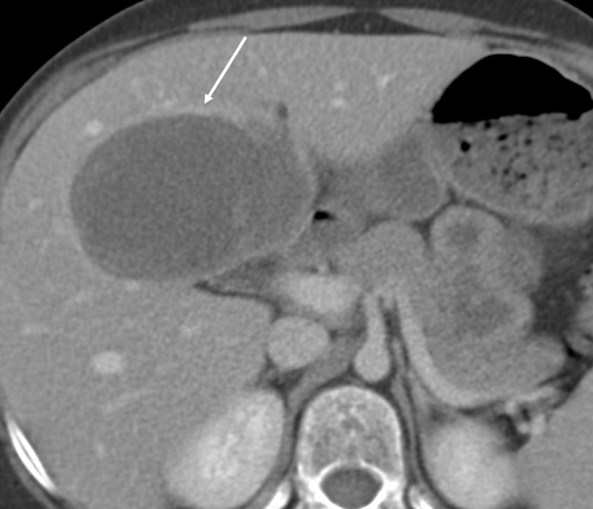

7 year old boy with an almost cystic appearing hepatic mass with thick peripheral enhancement. In the absence of fever, think of embryonal sarcoma as a possible diagnosis rather than an abscess; as this was correctly called.